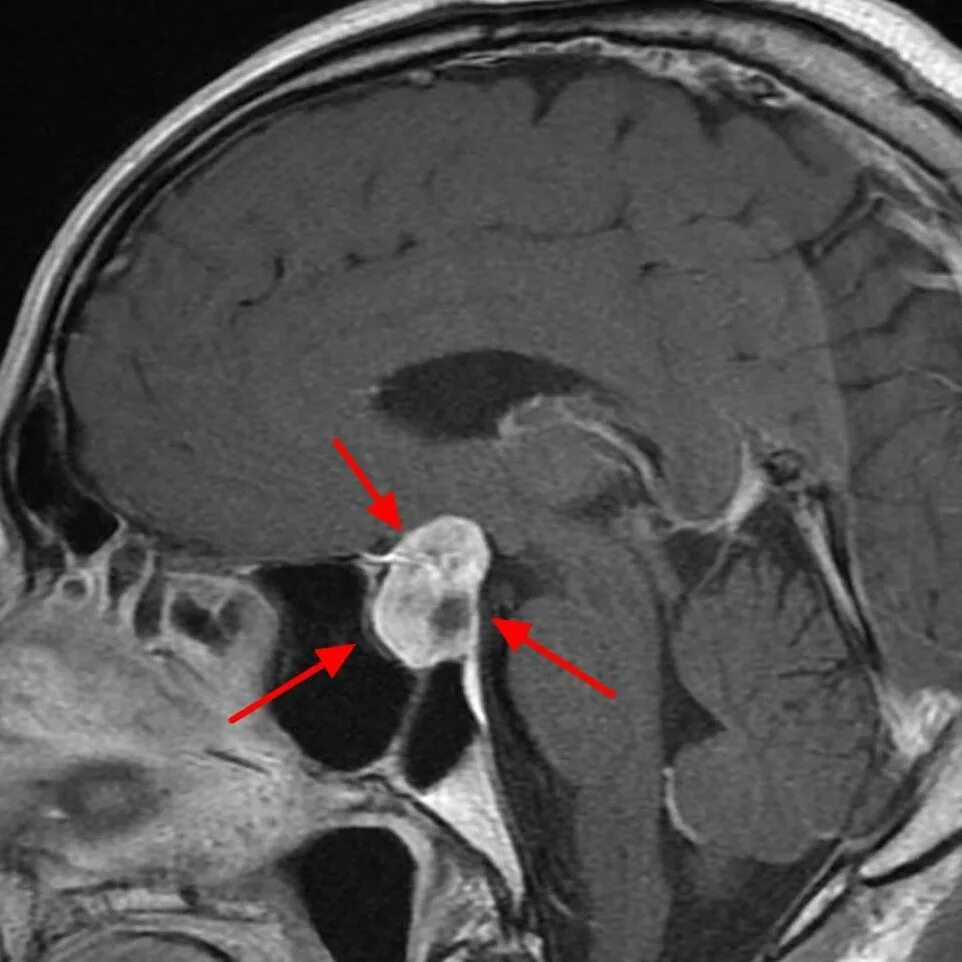

Опухоль гипофиза